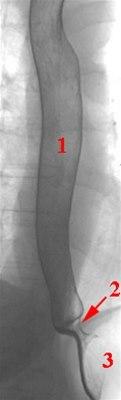

Endoskopi gjøres for å utelukke sykdommer som kreft og betennelse i spiserøret. Røntgen av spiserøret, der du svelger en kontrastgrøt, kan avdekke diffus spiserørskrampe, men viser ingen spesifikke forandringer ved nøtteknekker spiserør. Trykkmålinger i spiserøret er den undersøkelsen som kan stadfeste sykdommen og som skiller mellom diffus spiserørskrampe, nøtteknekker spiserør og hypertensiv nedre lukkemuskel i spiserøret.